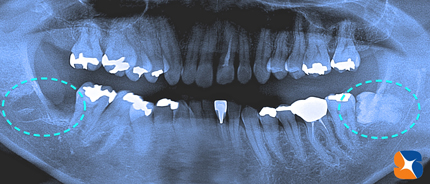

そして日を改め、帰省する前日の今日、残りの抜歯3本(上2本、下1本=点線)を行いました。